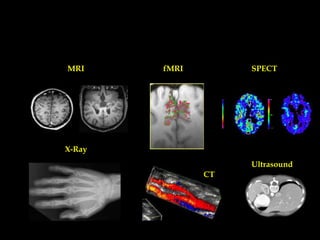

• X rays , CT

• Ultra

Sound, MRI

• SPECT

, PET

MRI

fMRI

SPECT

X-Ray

Ultrasound

CT